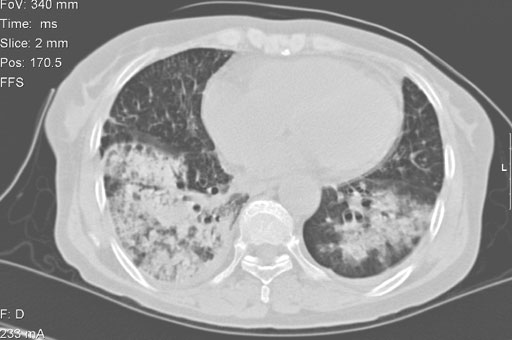

• 図3a 胸部単純CT

(肺条件)

• 図3b 胸部単純CT